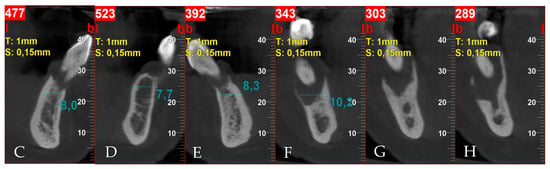

3.2. Surgery 1—Teeth Extraction and Periodontal Lesion Enucleation with Simultaneous Implantation

3.3. Surgery 2—Apically Positioned Partial-Thickness Flap (APPTF) in Combination with Free Gingival Grafts (FGGs)